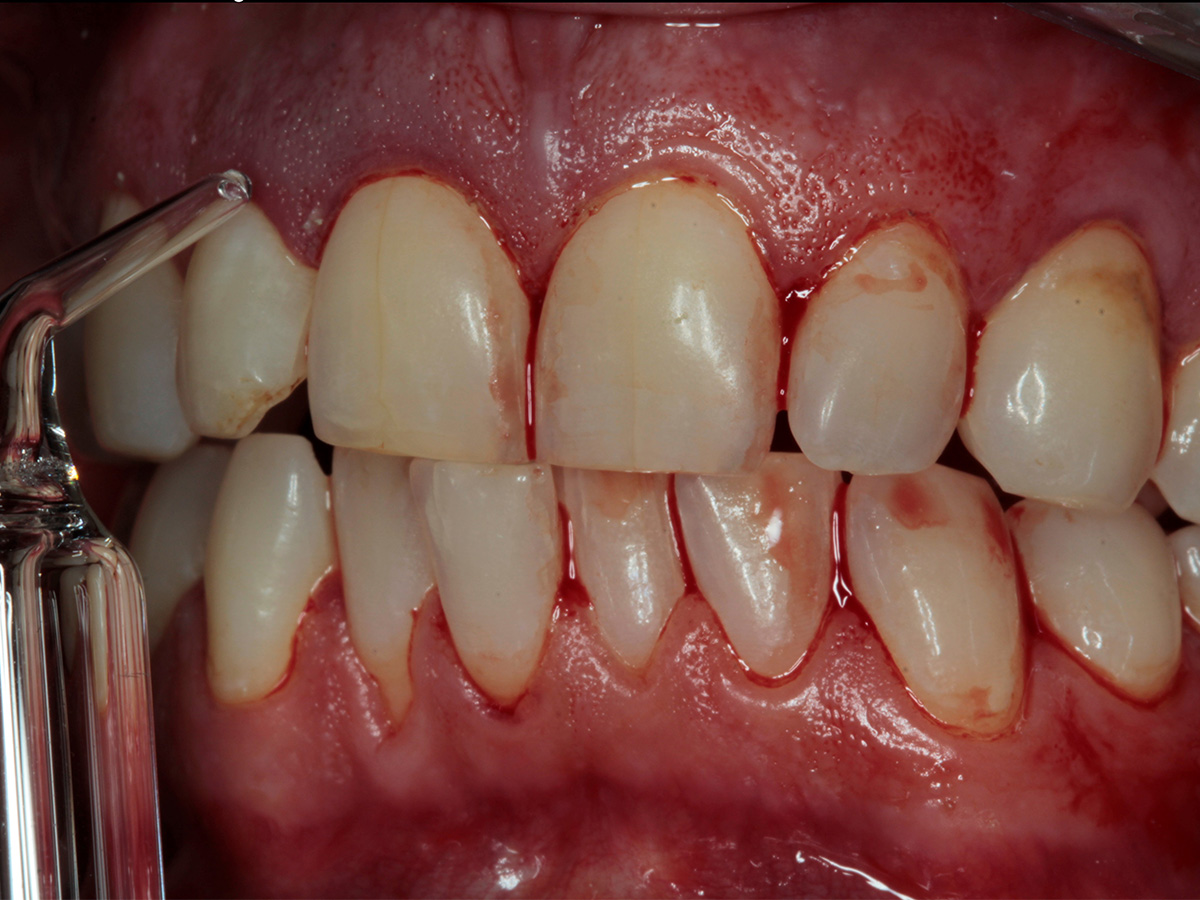

• Parodontale Krankheitsbilder erkennen